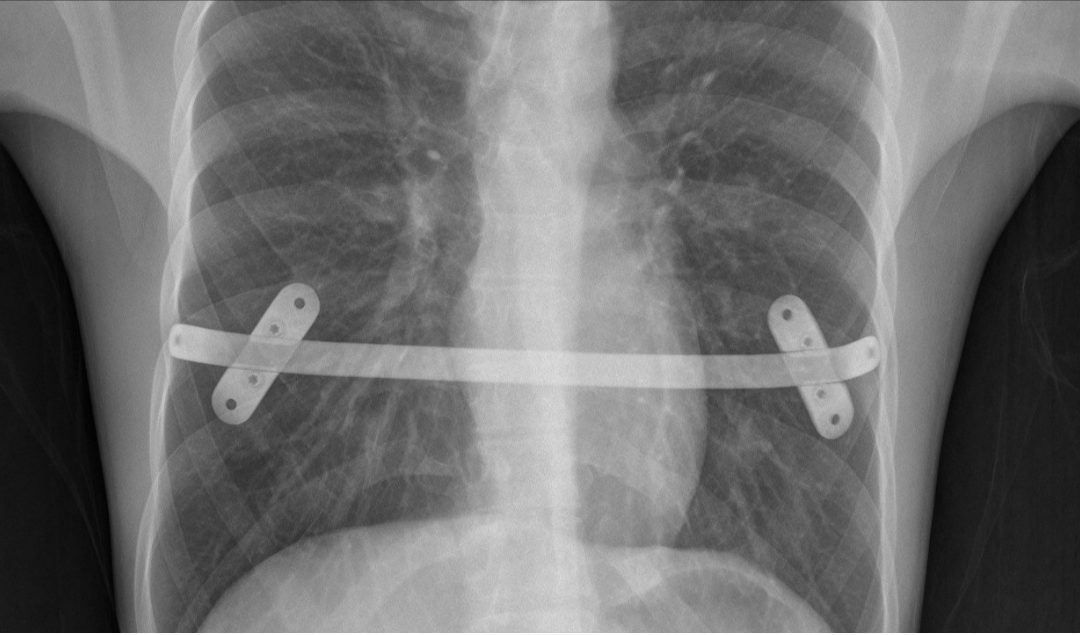

São barras transversais que permitem a fixação segura de mais de uma barra (Figura 3). Esse sistema virtualmente elimina a possibilidade de deslocamento das barras.

Figura 3 – Rx de tórax em perfil demonstrando as barras transversais que fixam duas barras metálicas. O sistema praticamente elimina a possibilidade de deslocamento das barras.